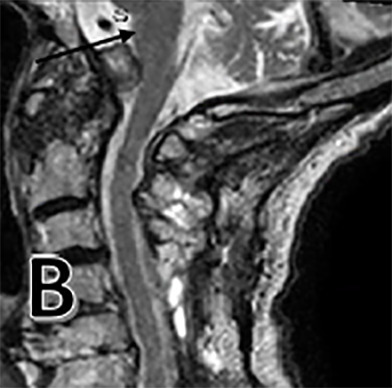

After his work-up was completed, the patient was found to have large odontoid pannus causing compression at the cranial cervical junction. We also noted a cyst associated with this pannus causing significant mass effect on the medulla (Figure 1 E). On MRI, this produced a T2 hyperintense signal at the medulla consistent with encephalomalacia, or medullary atrophy (Figure 1 A). The patient also had diffuse spondylosis, or degeneration, of the cervical spine along with central stenosis at the C4-5 and C5-6 level (Figure 1 C). Both an MRI of brain and CT angiogram were obtained and failed to reveal any other pathology. The posterior odontoid mass was found to be due to his rheumatoid arthritis.

The patient was followed up for two years. There was improvement in his motor weakness symptoms and he was eventually able to ambulate without an assisted device. Radiographic evaluation at the two-year follow-up mark showed marked reduction in the pannus and associated cyst with resolution of T2 hyperintense signal within the medulla (Figures 1 B, F). While there are reports in the surgical literature of smaller-sized pannus causing cervical spinal cord compression, we have been unable to identify any reports of such a large odontoid pannus with associated cyst and medullary compression.8